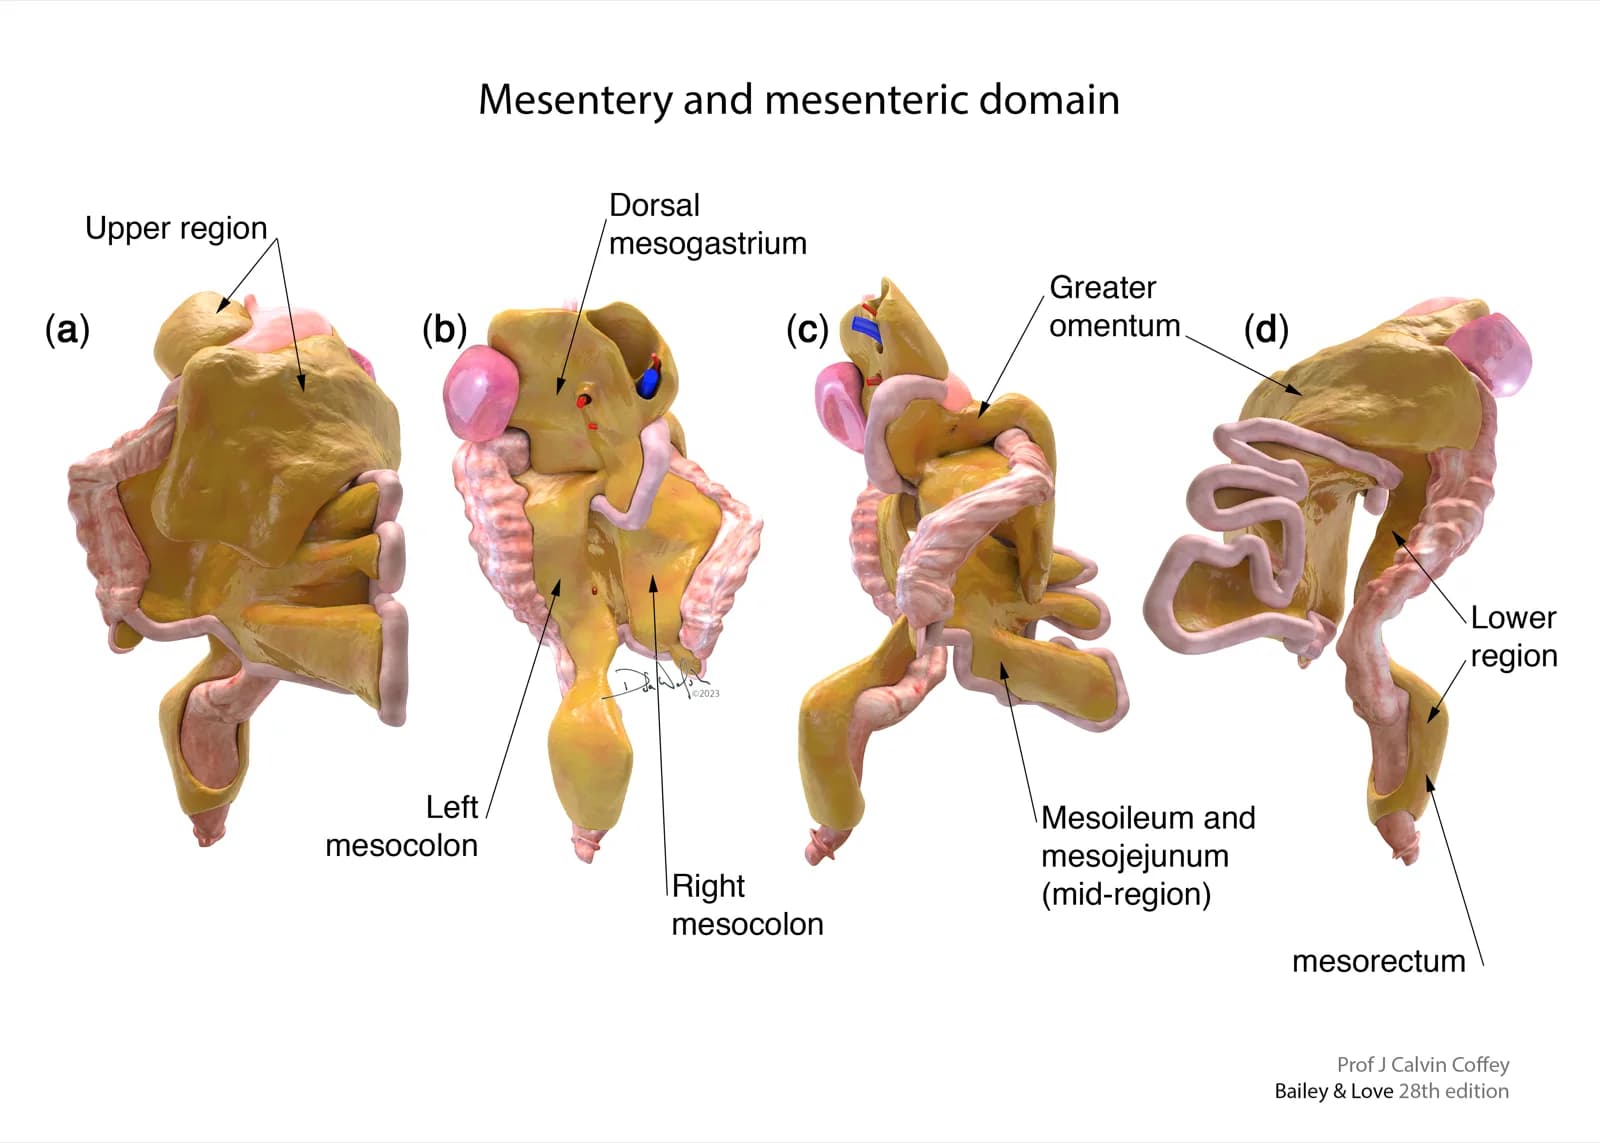

Mesentery: Advanced Anatomical Research is a long term, multidisciplinary research programme focused on redefining the understanding of mesenteric anatomy, development, and disease. The research has been ongoing for over 14 years, evolving alongside advances in surgical practice, imaging technology, and anatomical science.

The research programme began with a detailed exploration of embryology, establishing a developmental basis for understanding the mesentery as a continuous structure. This early phase focused on anatomical origin, differentiation, and positional development, forming the conceptual framework for later stages of research.

Following embryological analysis, the research expanded into cadaveric dissection, allowing direct anatomical validation of developmental concepts. Cadaver studies provided high resolution insight into structural continuity, fascial planes, and anatomical relationships not fully appreciable through imaging alone.

Understanding disease through the lens of a consistently defined mesenteric structure allowed for clearer interpretation of surgical findings and helped standardise anatomical language across clinical disciplines.

Findings from the research have been used to support education at multiple levels, including medical students, surgical trainees, and consultants. Material derived from this programme has been adapted for teaching, presentation, and professional discussion, ensuring that new anatomical insights are translated into clinical understanding.